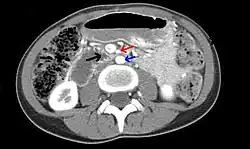

Abdominal and pelvic computed tomography scan showing duodenal compression (black arrow) by the superior mesenteric artery (red arrow) and the abdominal aorta (blue arrow). | |

Diagnosis is very difficult, and usually one of exclusion. SMA syndrome is thus considered only after patients have undergone an extensive evaluation of their gastrointestinal tract including upper endoscopy, and evaluation for various malabsorptive, ulcerative and inflammatory intestinal conditions with a higher diagnostic frequency. Diagnosis may follow X-ray examination revealing duodenal dilation followed by abrupt constriction proximal to the overlying SMA, as well as a delay in transit of four to six hours through the gastroduodenal region. Standard diagnostic exams include abdominal and pelvic computed tomography (CT) scan with oral and IV contrast, upper gastrointestinal series (UGI), and, for equivocal cases, hypotonic duodenography. In addition, vascular imaging studies such as ultrasound and contrast angiography may be used to indicate increased bloodflow velocity through the SMA or a narrowed SMA angle.[14][15]